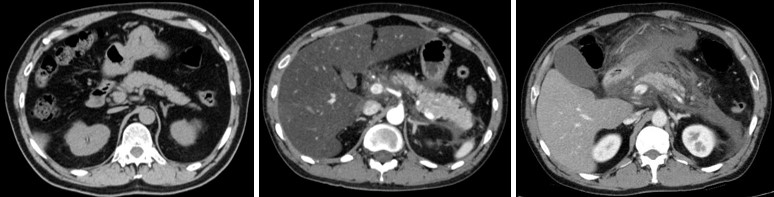

急性膵炎は、飲酒・高脂肪食の摂取・胆石が主な原因で、通常十二指腸に分泌されて、消化酵素として働く膵液が膵臓内で活性化してしまい、膵臓を自己消化してしまう疾患です。急激な腹痛・背部痛が症状として挙げられ、国内の年間患者数は約8万人と推定されています。急性膵炎患者の約80%は良好に経過しますが、残りの約20%は膵臓の壊死や多臓器不全を併発して重症化し、その場合の死亡率は約20%と言われています。重症急性膵炎の発症メカニズムは完全には明らかになっておらず、治療法も開発されていません。

近年、急性膵炎が重症化する最大の原因として、膵臓への細菌や真菌の感染が報告されています。急性膵炎の患者では、病原体や毒素の侵入から腸管を守るバリア機能が低下するため、腸内細菌が膵臓に感染し、細菌感染が引き起こす免疫反応によって重症化することがわかっています。腸管バリア※2 機能の低下によりカンジダ菌などの真菌が感染した場合も、同様に真菌感染に伴う免疫反応により重症化する可能性が考えられますが、詳細なメカニズムは明らかになっていません。

研究グループは、自分たちの先行研究をもとに、セルレイン※4 という分子をマウスに繰り返し投与して急性膵炎を誘導しました。この急性膵炎モデルマウスに対して、まずはLRRK2を特異的に抑制する阻害薬を投与すると、膵炎を引き起こす炎症性サイトカイン※5 反応が低下し、急性膵炎が軽症化することが分かりました。また、全身の細胞にLRRK2が強く発現し、LRRK2の機能が活性化しているLRRK2トランスジェニックマウス(LRRK2 Tgマウス)に膵炎を誘導したところ、阻害薬投与の場合とは逆に、炎症性サイトカイン反応が増加し、急性膵炎が重症化することが判明しました。ここから、LRRK2の機能亢進と低下が、それぞれ膵炎の重症化と軽症化に関与することを発見しました。

膵炎の発症には、腺房細胞※6 と免疫細胞の両方が関わることが知られています。どちらの細胞のLRRK2が影響を及ぼしているかを検証するため、LRRK2 Tgマウスと野生型マウスを用いて骨髄移植※7 実験を行いました。その結果、免疫細胞であるマクロファージ・樹状細胞※8 のLRRK2が、急性膵炎の重症化に必須であることが分かりました。

さらに、急性膵炎の重症化に、細菌と真菌のどちらがより影響するか検証するため、腸管内の細菌と真菌をそれぞれ抗細菌薬と抗真菌薬で除去し、症状の変化を確認しました。その結果、抗細菌薬による細菌の除去はLRRK2 Tgマウスの膵炎の重症度に影響を与えず、抗真菌薬による真菌の除去により、膵炎は著しく軽症化しました。さらに、重症膵炎を発症したLRRK2 Tgマウスの膵臓のマクロファージ・樹状細胞は、細菌成分ではなく真菌成分に反応し、炎症性サイトカインを多く産生しました。